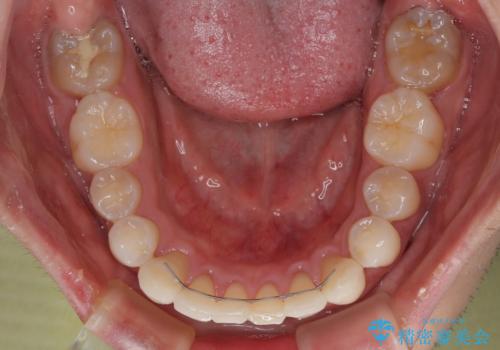

- 前歯のデコボコや八重歯を気にして来院された患者様です。

左右ともに奥歯の咬み合わせに問題があり、上顎臼歯が前方位にある状態で、結果として上顎前歯全体が前方位かつ叢生になっていました。

また、左右ともに上顎最後臼歯が頬側に転移していたため、補助装置を用いて舌側に移動をさせながら、上顎前歯を引っ込むように移動させることとしました。

口元の突出感を解消させるため上顎左右第一小臼歯2本を抜歯して、ワイヤー装置にて矯正治療を行うこととしました。

上顎のみの抜歯矯正であったため、治療期間が長期化することが予想されましたが、何とか3年弱の期間で想定通りの仕上がりで終えることができました。